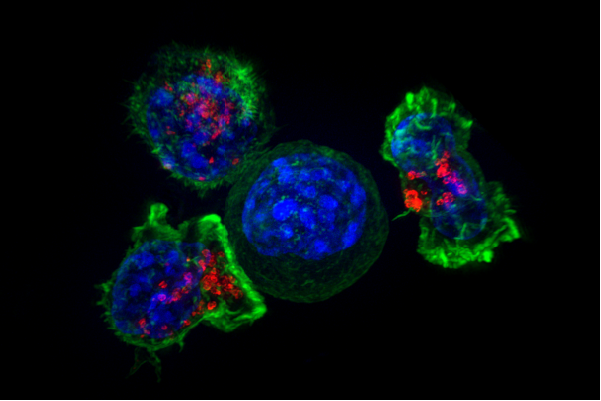

Immagine: le cellule killer T circondano una cellula tumorale. Credit: NIH